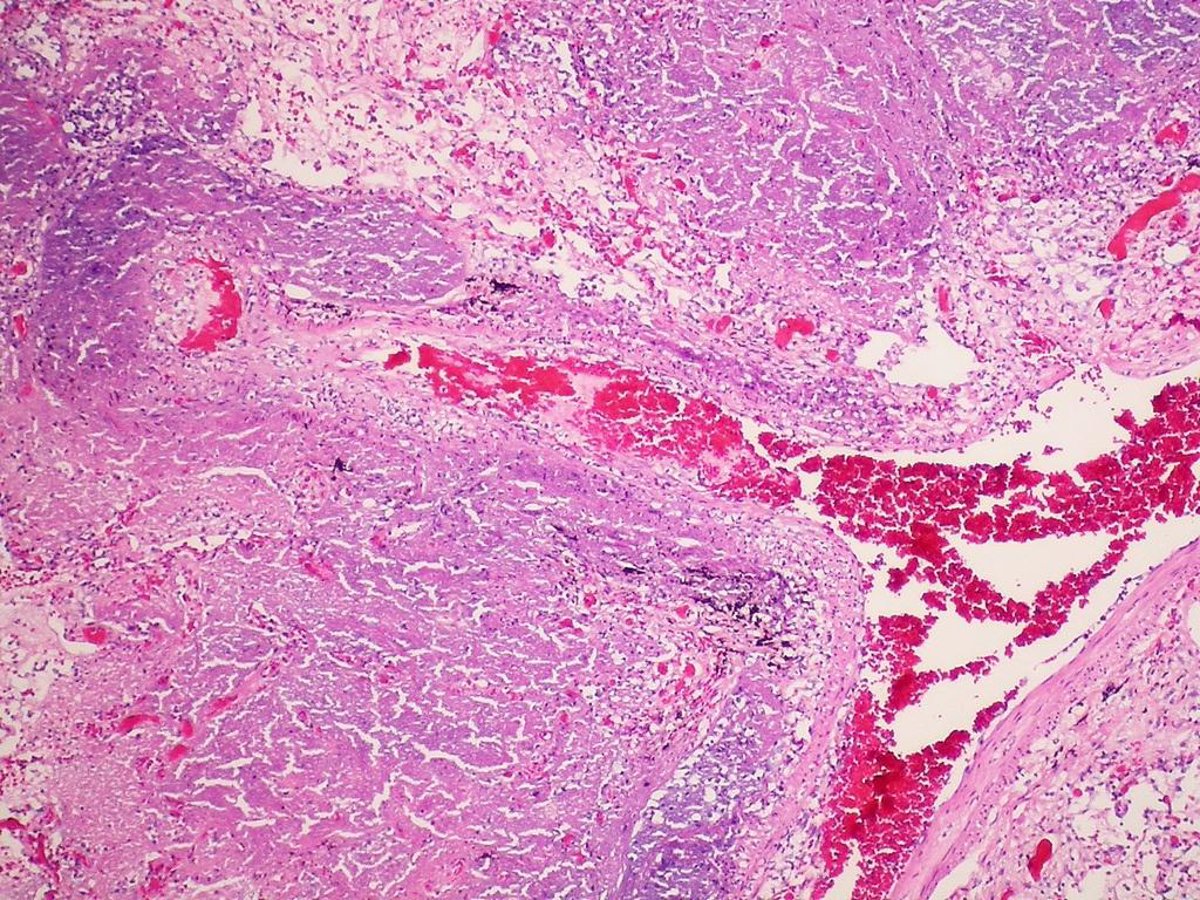

Tuberculosis

FLICKER/ PULMONARY PATHOLOGY